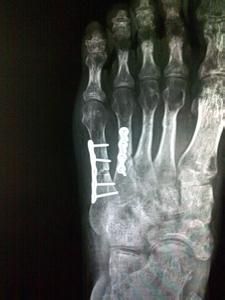

手術治療

對活動要求較高者和運動員,提倡手術治療。手術治療也適用於骨延遲癒合和骨不癒合患者以及關節內骨折者。

但即便是手術治療,由於骨折的特殊性,那個位置的骨頭也不能保證能夠完全癒合。因為那裡供血較差,而且還有腓骨短肌和各種肌腱存在,另外還有兩塊小肌肉附著在骨頭上,它們都將影響到骨頭的癒合。